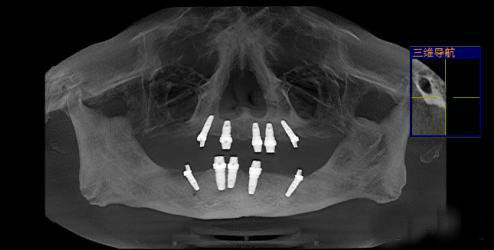

先将下颌牙齿拔除,恢复十天后,进行上颌牙齿种植修复。上颌牙齿采用韩国3D微创仿生种植技术,即拔即种,完成左上1、4、5、7及右上1、4、5、7,共植入8颗种植体。韩国3D微创仿生种植系统的种植体材料有别于现有种植体材料,率先采用五级纯钛,不会对人体产生任何金属过敏现象及副作用,与人体相容性远高于现有四级纯钛种植体。